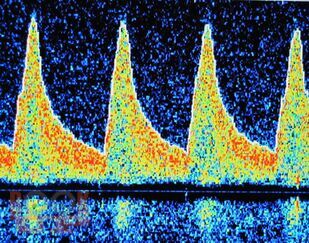

В учебно-методическом пособии для врачей представлена сущность метода транскраниальной допплерографии, основные параметры допплерограммы, применение описанных методик в оценке регуляции мозгового кровообращения. Также дано подробное описание допплерографических паттернов кровотока с их развернутой характеристикой.